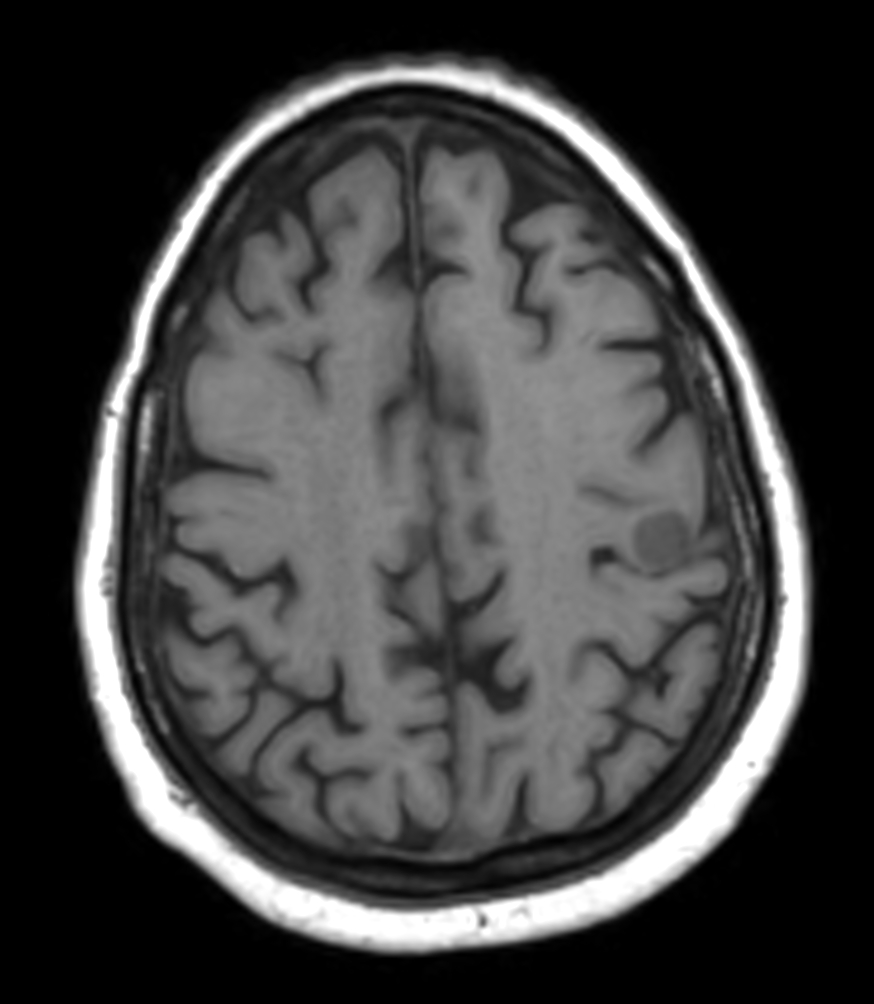

Female with one metastasis of pulmonary cancer underwent MRI simulation in the radiotherapy positioning mask on Ingenia MR-RT 1.5T before stereotactic radiation therapy with 25 Gy in 3 fractions.

Axial 3D T1w FFE pre contrast